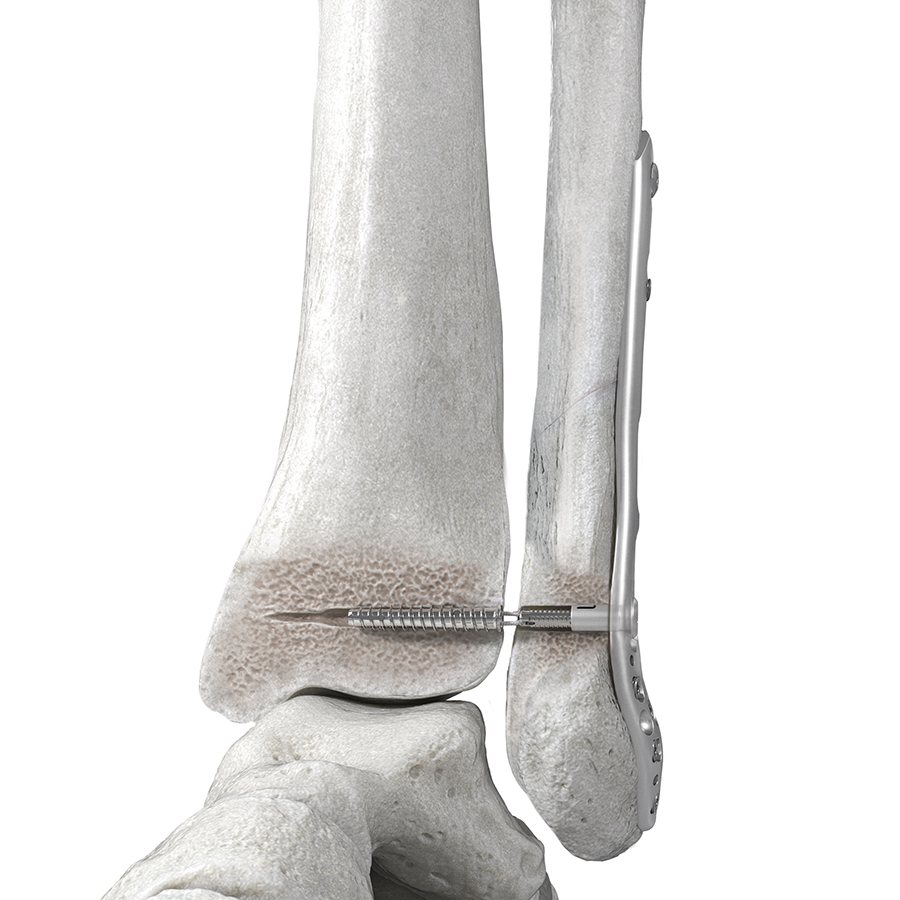

The FIBULINK™ Syndesmosis Repair System (Fig 1) combines the benefits of fixation of a screw and the flexibility of a suture. A short, high-strength suture bridge helps to restore the physiologic ankle motion.

The implant is a multicomponent anchor system consisting of four main components (Fig 1):

- Fibula Tensioning Cap: interfaces with the Fibula Link. A rotation of the Tensioning Cap applies tension to the construct.

- Fibula Link: transfers the tension applied by the Fibula Tensioning Cap to the Suture Bridge. As such, it functions as an interface in the primary tension mechanism.

- Suture Bridge: applies compression between the fibula and the tibia via transferring the tension between the Fibula Link and the Tibia Screw. The 4 mm long Suture Bridge consists of four strands of #1 Ultra High Molecular Weight Polyethylene.

- Tibia Screw: functions as an anchor in the tibia.

The 1.4 mm K-wire must be placed in appropriate position. Either in the center of the fibula and directed slightly anterior into the tibia, or - if used with a plate - through the center of the plate hole to allow free passage of the device. The step-drill bit should be advanced with caution to avoid penetration into the tibia. The tibia screw must be inserted until just flush with the lateral cortex of the tibia. Internal and external oblique imaging with the C-arm may be necessary to confirm appropriate depth of insertion.

The Tensioning Knob is used to fine tune and readjust the tension in the Suture Bridge intraoperatively (Fig 3). Clockwise or counterclockwise rotation of the Tensioning Knob will advance or reverse the Fibula Tensioning Cap, thereby adjusting the tension in the suture bridge in a two-way tension control to achieve the desired level of correction.

The FIBULINK fixation concept does not require medial soft-tissue disruption and helps improve procedural efficiency by delivering fixation through a single lateral incision. Since it does not rely on hardware placement on the medial tibia it eliminates medial side complications, such as damage to neurovascular structures and soft-tissue entrapment associated with suture button constructs. It also limits interference with the placement of additional hardware on the medial side (eg, medial malleolar screws), which might be required because of the injury (eg, high-energy injury).

The short, high-strength suture bridge (Fig 4) enables physiological motion by spanning the distance between the medial side of the fibula and the lateral side of the tibia. Suture button constructs typically rely on long suture bridges between the lateral side of the fibula and the medial side of the tibia. The long suture distance can lead to suture toggling and tunnel widening compromising the fixation stability and changing the syndesmosis gap.